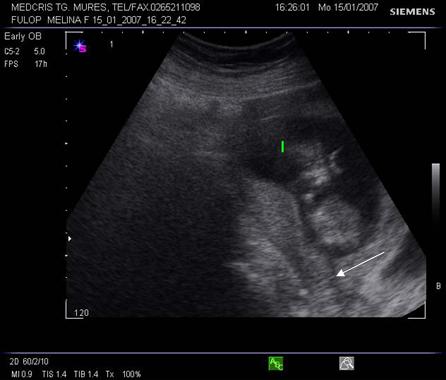

Fig. nr. 66. Aceeasi sarcina, ca in figura precedenta, la 12 saptamani , fara imagini patologice la polul inferior ovular, marcat cu sageata

Fig nr 68 Decolare de pol inferior la ecografia abdominala ( sageata )